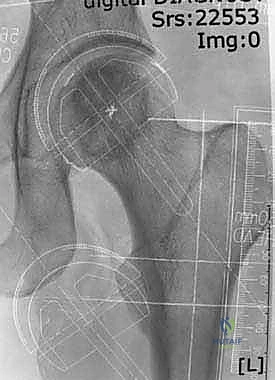

3. نحت وتشكيل رأس عظمة الفخذ

بدلاً من قطع الرأس، يستخدم الجراح أدوات ميكروسكوبية ومثاقب دقيقة جداً لإزالة الغضروف التالف وطبقة رقيقة من العظم المريض، ليتم "نحت" رأس العظمة ليصبح جاهزاً لاستقبال الغطاء المعدني بشكل مثالي.

4. تركيب الغطاء المعدني (Femoral Component)

يتم تثبيت التاج أو الغطاء المعدني الأملس فوق رأس عظمة الفخذ المنحوت، وغالباً ما يتم تثبيته باستخدام مادة أسمنتية طبية خاصة لضمان ثباته المطلق.